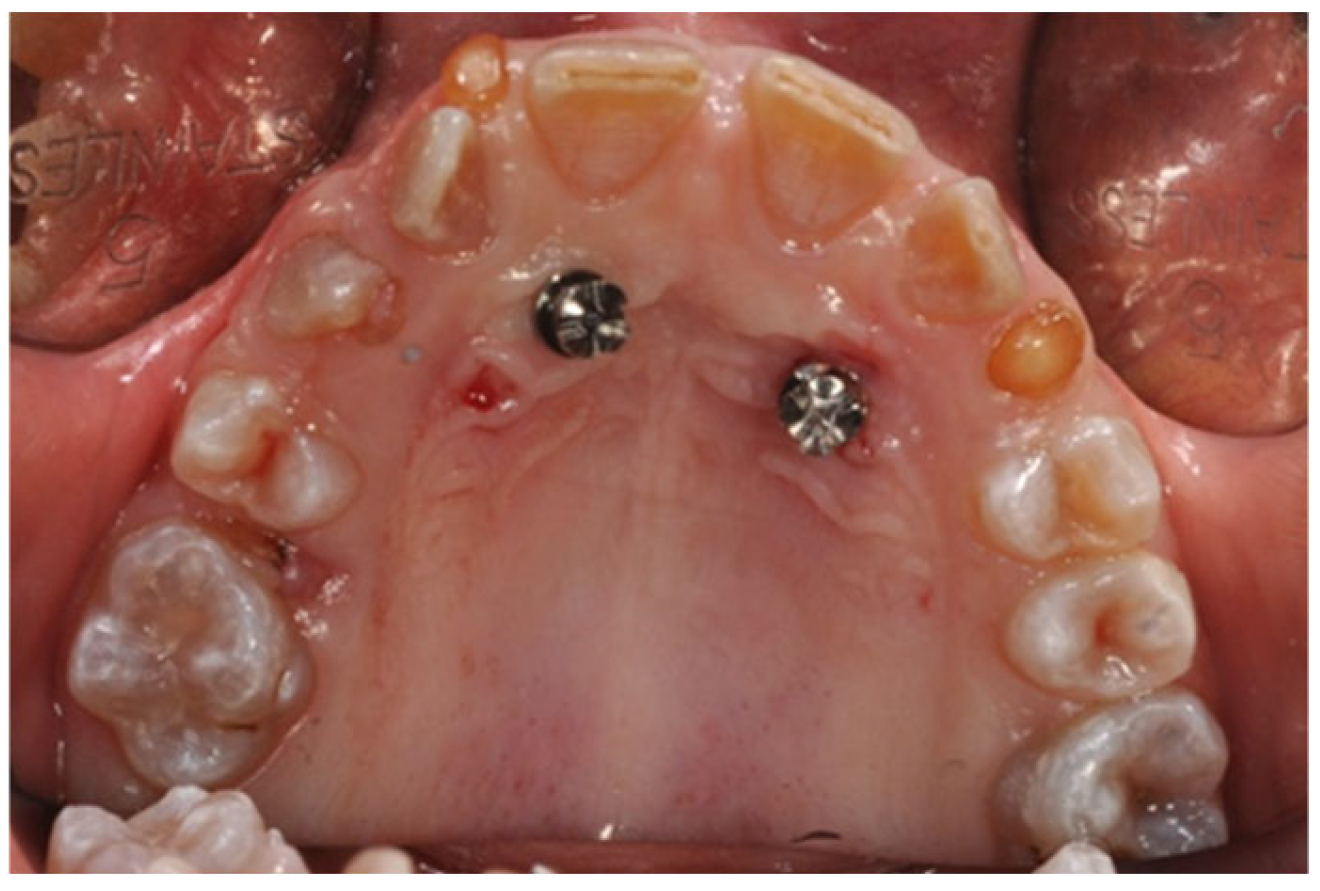

2.1. MSE Treatment in Patient with Ectodermal Dysplasia